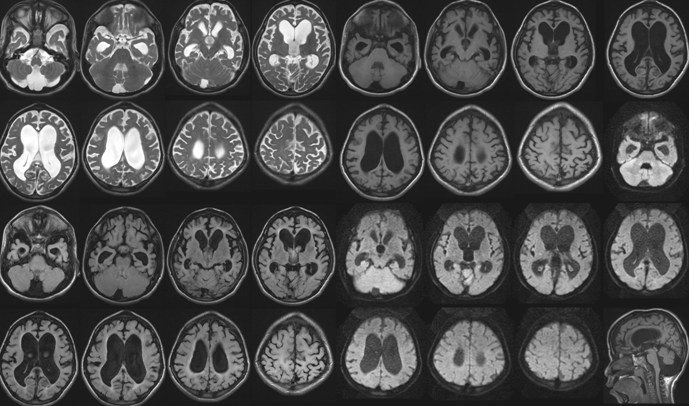

病例9

女性,31岁,头痛半月余,加重1周于于2020年3月25日入院。 患者半个月前出现头痛,多睡眠中痛醒,持续数分钟,1次/天。1周前头痛症状加重,呈周期样发作(头痛持续数分钟,缓解数分钟),间歇半个小时至1小时不等,持续时间及发作频率渐增加,约7-8次/天,基本卧床状态(除吃饭,二便),从坐姿到站姿时头痛明显,睡觉时头痛减轻,多痛醒。3天前患者出现视物不清,看远处物体时明显,视力损害逐渐加重。病程中患者有自觉发热,自测体温不高,无恶心呕吐。

2020年4月7日复查颅脑核磁:

腰椎穿刺,脑脊液压力450mm。脑脊液常规:有核细胞:23×10^6/L,淋巴细胞96%。脑脊液生化:蛋白0.27g/L,氯123mmol/L,葡萄糖:3.48mmol/L脑脊液涂片:墨汁染色见新型隐球菌。脑脊液隐球菌荚膜抗原阳性。

答案:隐球菌性脑膜炎。由扩大的VR间隙融合而成的胶质假性囊肿,直径>5mm,单发或多发,可聚集成簇状囊肿。病变分布与VR间隙扩大分布一致,常位于基底节区,呈对称性分布,为隐球菌荚膜所产生的粘液,胶状物质充填而扩张,形成的小囊腔,含大量隐球菌,呈肥皂泡状,具有一定特征性。 呈类圆形,边界清楚,T1WI呈低或稍低信号,T2WI呈稍高或高信号,增强可强化(增强被认为是免疫完整宿主的慢性炎症反应),弥散可受限。

病例10

患者男,52岁,因“幻觉胡言 乱语3天,伴视物重影2天”入院。

答案:韦尼克脑病。易受到硫胺素(维生素B1)缺乏造成的损害的部位包括丘脑、乳头体、导水管周围和室旁区域、蓝斑、 颅神经核和网状结构。临床表现包括以下三个症状:眼肌麻痹、共济失调和脑病症状精神状态或智能状态改变。